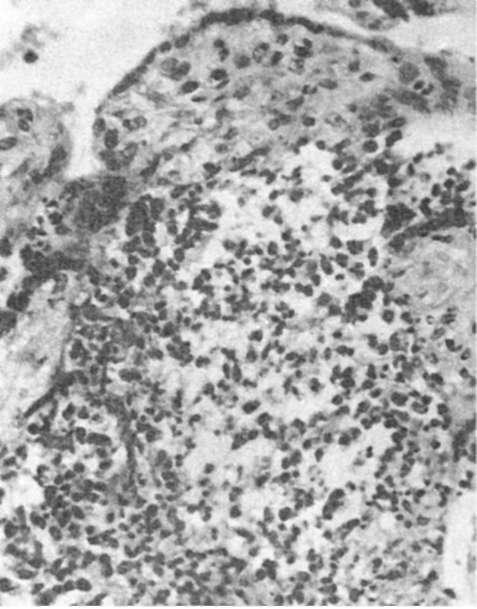

Рис. 303. Базальный децидуит при вирусно-бактериальной пневмонии у матери. Массивная лейкоцитарная инфильтрация (препарат И.О. Харит)

Для гноеродной бактериальной инфекции характерно серозно-гнойное или гнойное воспаление, иногда с развитием флегмоны или абсцессов. При листериозе инфильтраты имеют лейкоцитарно-гистиоцитарный характер (рис. 304) в строме ворсин, наблюдаются отек, эндартерииты, тромбофлебиты, иногда обнаруживаются листериомы. Встречается небольшое число листерий. При туберкулезе в плаценте возникают казеозные очаги, бугорки с эпителиоидными и гигантскими клетками, чаще поражается базальная пластинка.